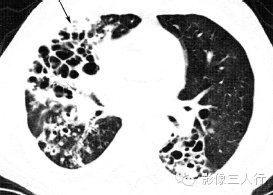

| 支气管扩张

(图1) |